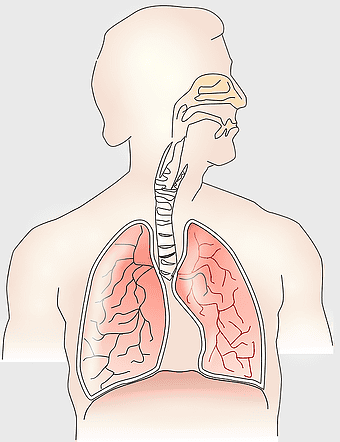

- heart and lung anatomy

human lung anatomy, respiratory system illustration, heart and lungs diagram, bronchus structure, pulmonary function, thoracic cavity, medical imaging analysis -

lungs illustration, respiratory system diagram, human lungs anatomy, pulmonary alveolus structure, bronchial tree visualization, trachea and bronchi, lung lobes detail -

Respiratory system anatomy, human breathing process, pulmonary alveoli structure, respiratory therapist training, respiratory health education, lung function diagram, respiratory disease prevention -

human lungs illustration, respiratory system anatomy, carina of trachea, blood vessel in lungs, pulmonary function, respiratory tract diagram, bronchial tree structure -

Lung Respiratory system, trachea and bronchus, pink lungs illustration, breathing anatomy, pulmonary health, respiratory function, medical education visuals